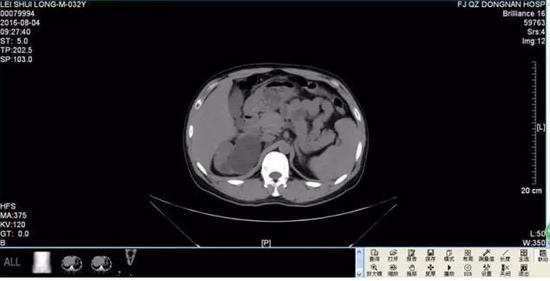

几天后,雷先生来到医院做进一步检查,令雷先生和医生们吃惊的是,腹腔巨大囊肿其实是右侧重复肾输尿管肿大,最大直径竟有13厘米,而正常人的输尿管只有0.8厘米粗,最终,雷先生被确诊患有罕见的巨输尿管症,医院根据雷先生的情况对其右侧重复肾上半肾、重复输尿管进行了切除,术后恢复良好。

医院泌尿外科主任庄海南介绍,这种病属先天性双侧双肾、双输尿管重复畸形,十分罕见,大约10万人里才会遇到一个。据了解,当人胚胎在第六周时,中肾管末端通入泄殖腔处,向背侧突出一小的盲管,称为输尿管芽。输尿管芽迅速成长发育成肾盂,分支形成肾盏,再分支形成小盏、集合管。如分支过早,则形成重复的输尿管畸形,且重复输尿管常伴发重复内脏。